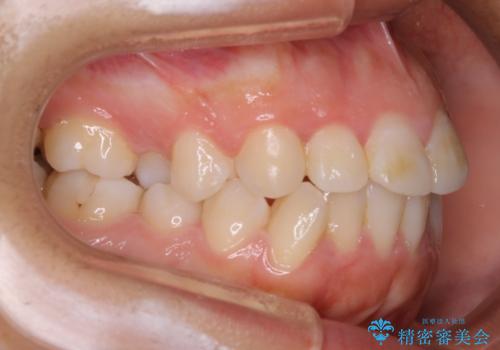

抜歯矯正

叢生(ガタつき)が強い場合や上下もしくはどちらかの歯が前方に出ている場合、その問題を解決するためのスペース作りのため抜歯をすることがあります。

多くのケースは第一小臼歯を抜歯することで並べたい前歯のすぐ近くにスペースを作りガタつきや出っ歯を改善していきます。